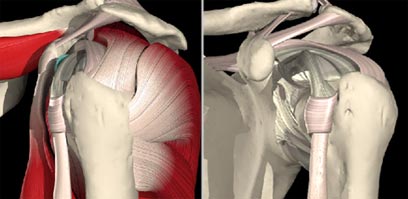

קרע של הלברום- מתבטא בפריקה של הכתף (צילום: מרכז רפואי איכילוב)

׳השרוול המסובב׳ הוא קבוצה של ארבעה שרירים והגידים שמחוברים אליהם, שעוטפים את ראש עצם הזרוע במעין שרוול. השרירים והגידים האלה אחראים על הנעת הכתף ועל טווח התנועה שלה ומתחלקים לקדמי, עליון ושניים אחוריים. מבין כולם הפגיע ביותר הוא הגיד העליון, שנושא את רוב העומס, ובעיה בו תורגש בקושי ובכאב בעת הרמת היד מעל גובה הכתפיים. תמונה אופיינית של חולה עם קרע בגיד הכתף כוללת כאב עז, קושי בהרמת היד וחולשה בעת ניסיון להרים חפצים.

מבנה מפרק הכתף וטווח התנועה הרב שלו מעמידים את הכתף בסכנה של חוסר יציבות עד כדי תת פריקה או פריקה מלאה. במצב של תת פריקה ראש הזרוע מחליק באופן חלקי אל מחוץ למכתש, ואילו בפריקה מלאה ראש הזרוע מתנתק מהמכתש עד איבוד המגע ביניהם. המצבים האלה יופיעו בדרך כלל בעקבות טראומה לכתף. הבעיה במצבים האלה, מעבר לאי נוחות לחולה, היא בנזק שנגרם למייצבי המפרק, שמוביל לאי יציבות קבועה ולפריקות חוזרות.

במהלך פריקה עלולים להיגרם כמה נזקים למפרק הכתף, כמו שבר דחיסה של ראש עצם הזרוע ותלישה של רקמה בקדמת המכתש. לעיתים הנזקים חמורים יותר וכוללים שבר של המכתש בדרגות חומרה שונות, שברים עם תזוזה של ראש עצם הזרוע, קרע בגידי השרוול המסובב, פגיעות עצביות או פגיעות בכלי דם.